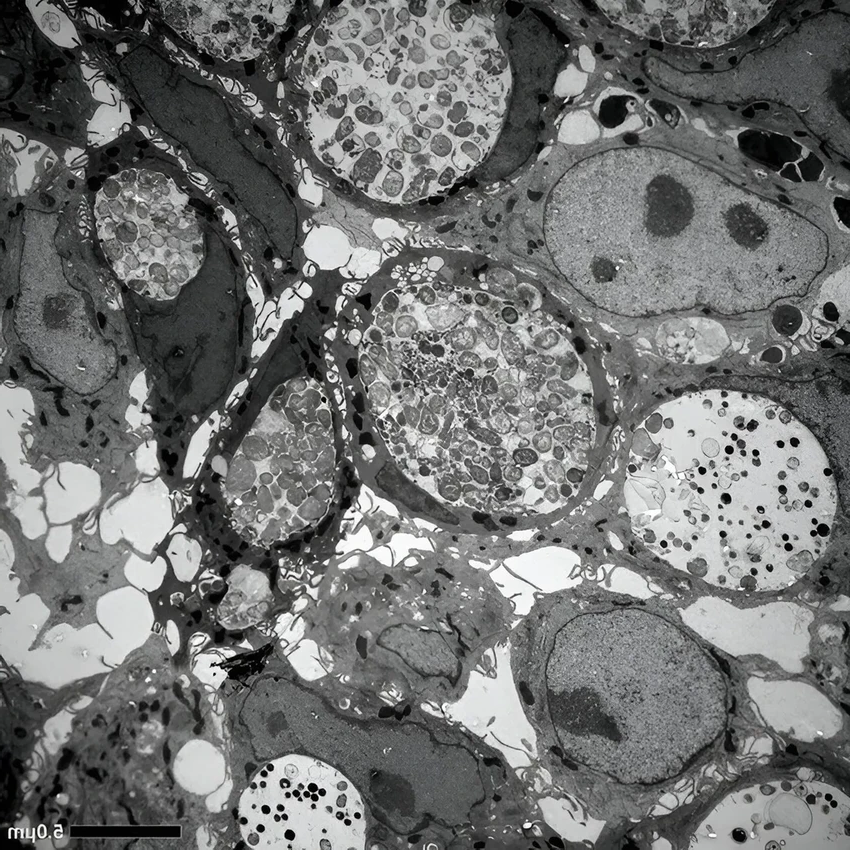

В исследовании, опубликованном в журнале PLOS Pathogens, немецкие ученые из Вюрцбургского университета пошли на хитрость. Они вырастили в лаборатории миниатюрные, но функциональные копии человеческого кишечника — так называемые органоиды. И поселили туда хламидий.

Результат оказался одновременно впечатляющим и пугающим. Бактерии не просто прижились. Они с легкостью проникли вглубь, через слой клеток, связанный с кровеносными сосудами, и затаились там. Они приняли устойчивую, «спящую» форму, способную долго сохраняться в организме. Не правда ли, гениальная стратегия выживания?